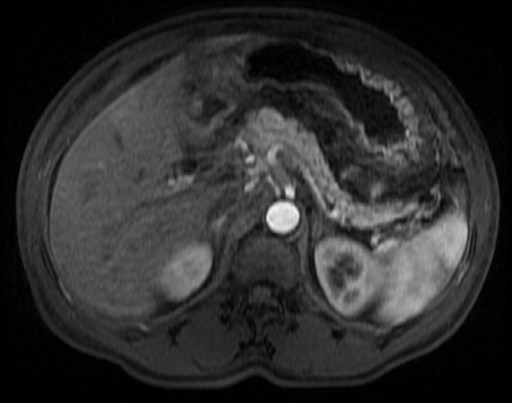

A 59-year-old African-American man was admitted with abdominal pain of three-day duration, associated with emesis and hiccups. Past medical history was significant for diabetes mellitus. He admitted to alcohol use once to twice a month. On examination, there was mild epigastric tenderness. Laboratory studies showed leukocytosis (15,700 cells/mm3); hematocrit was 45.4% (reference range: 36.0-46.0%), serum creatinine was 1.4 mg/dL; transaminases were mildly elevated (AST 89 U/L, ALT 65 U/L); alkaline phosphatase and bilirubin were normal. Amylase and lipase were 108 U/L and 35 U/L, respectively. CT scan of the abdomen with intravenous contrast showed stranding around the head of the pancreas suggestive of acute pancreatitis. Ultrasound of the abdomen showed a common bile duct diameter of 9 mm, no gallstones, and heterogeneous pancreatic head consistent with pancreatitis versus a mass lesion. MRI of the abdomen with contrast showed prominent inflammatory changes surrounding the pancreas, with no necrosis or pseudocyst formation (Figure 3). The hepatitis profile was negative. Patient was treated with intravenous fluids, insulin and antiemetics. Repeated measurements of amylase and lipase were normal. Patient had an uneventful recovery and was discharged home on day 6.

Figure 3. MRI of the abdomen with contrast (Case #3). |